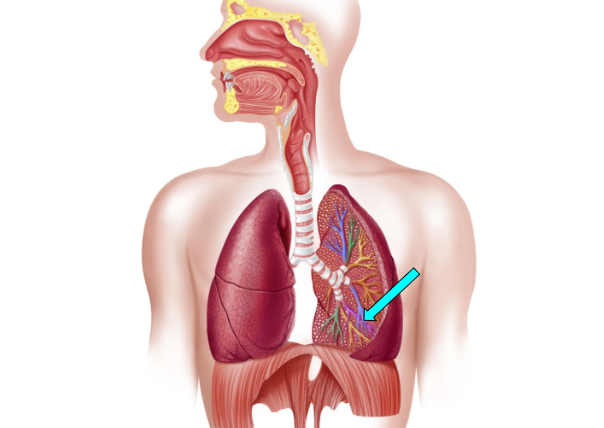

Bronchioles

small airway that delivers oxygen to the alveoli for gas exchange

Bronchi

carry oxygen to and from the lungs

Alveoli

facilitate gas exchange through the lungs & bloods to exchange oxygen & carbon dioxide during respiration

Bronchus (pic)

Bronchioles (pic)

Alveoli (pic)